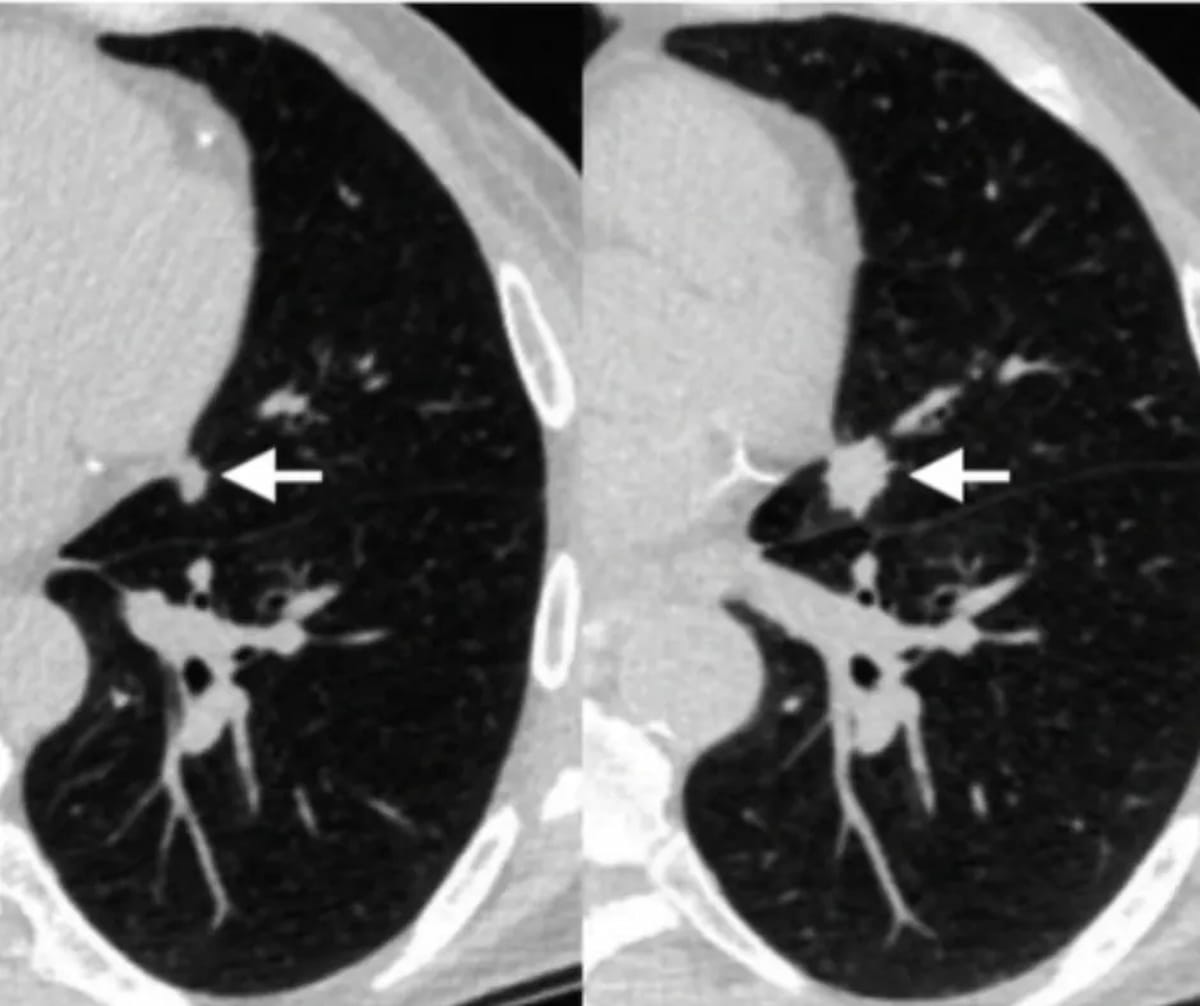

In a multicenter cohort of patients with interstitial lung disease (ILD), a deep learning classification tool demonstrated an 81 percent sensitivity rate and a 77 percent specificity rate for predicting usual interstitial pneumonia on computed tomography (CT) scans.